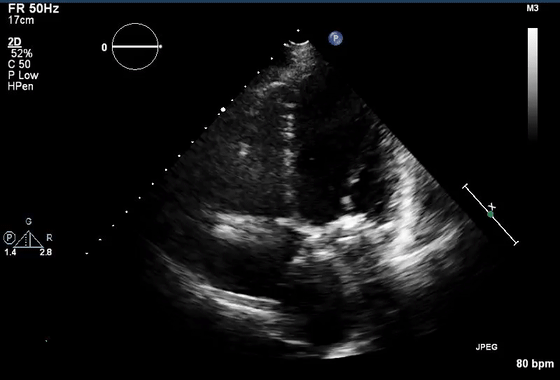

7、近场杂波

由于探头换能器本身的高振幅振荡,近场结构有时会被遮蔽,造成所谓的近场杂波。这在怀疑有心尖室血栓的病例中尤其重要(图7,视频10)。谐波成像的引入和换能器设计技术的进步已经减少了这种伪影的发生。

图7 心尖四腔视图中的近场杂波(箭头),疑似心尖血栓。(视频10)显示正常的心尖心肌动力学,杂乱回波和心肌运动之间没有关系。